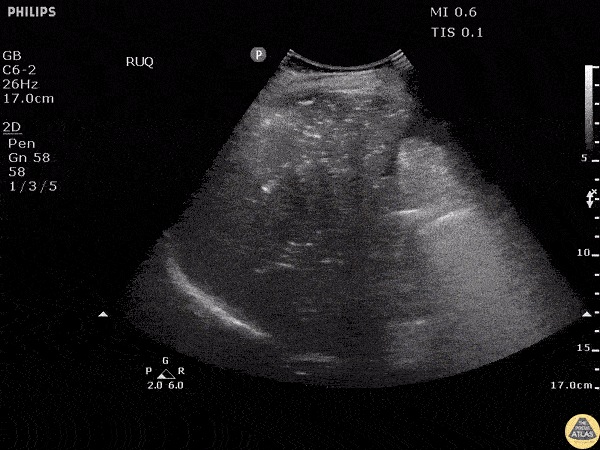

Biliary - Portal Venous Gas

RUQ ultrasound reveals air within the portal venous system in a patient with ischemic colitis. Something that can be difficult to distinguish from pneumobilia. Image courtesy of Robert Jones DO, FACEP @RJonesSonoEM Director, Emergency Ultrasound; MetroHealth Medical Center; Professor, Case Western Reserve Medical School, Cleveland, OH View his original post here